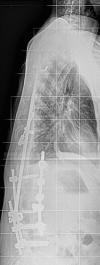

Case presentation: We report the case of a 46-year-old Caucasian woman who underwent surgery due to idiopathic scoliosis with a Harrington Instrumentation (T4 to L3) 30 years ago. During the operation she was infected with hepatitis C while receiving erythrocyte concentrates and has suffered from liver cirrhosis since then. She presented with a sudden pain in her lower back and paraesthesia in both her legs but no other neurological symptoms. A computed tomography scan showed a bilateral pedicle fracture of L3 and an additional compression fracture of L4. In the first session we performed a dorsal stabilization with massive intraoperative bleeding and a postoperative failure of liver synthesis. In a second session an additional ventral augmentation was done. After the second operation she developed a hepatorenal syndrome. Both operations left the patient in a very critical state which led to a prolonged stay in the intensive care and rehabilitation unit. At her 12-month follow-up visit, she was free of complaints.